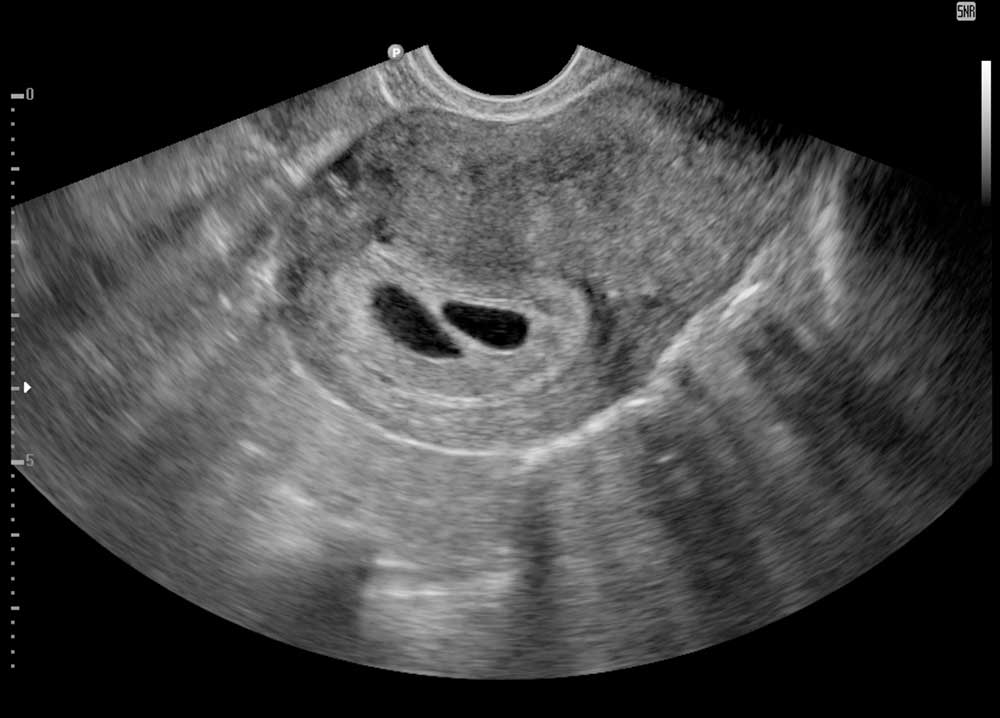

![[Ads] Ultrasound Baby Scan 3 2d twin 5w](https://klinikazurose.com/wp-content/uploads/2025/03/2d-twin-5w.jpg)

See your little one for the first time and hear their heartbeat. This Early 2D Scan helps confirm your pregnancy, and estimate your due date. At this stage, the fetus’ vital organs begin to take shape.